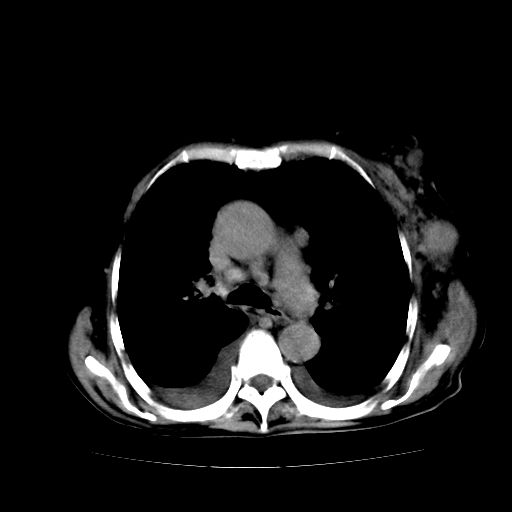

女70y乳腺ca(针吸活检)

癌性淋巴管炎,肝脏转移,瓷胆囊

1)左侧乳腺癌并左侧腋窝及纵隔淋巴结转移,两肺淋巴道转移(癌性淋巴管炎),肝脏多发性转移。2)双侧胸腔积液。3)慢性胆囊炎。

1、左侧乳腺癌;

2、左腋窝、纵隔淋巴结肿大(转移性);

3、双肺癌性淋巴管炎;

4、双侧胸腔积液(考虑淋巴回流障碍所致);

5、肝转移瘤;

6、瓷胆囊。